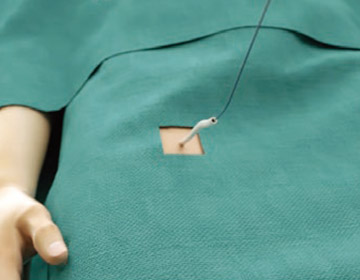

手技手順

1

1

経皮的アプローチでガイドワイヤとダイレーターを右大腿静脈に挿入します。

2

2

X線と経食道心エコー(TEE)下で留置手技を実施します。経心房中隔穿刺システムを用いて心房中隔を通過します。

入院

手術前日に入院いただき、内服薬の確認・血液検査・麻酔科術前診察(入院日によっては外来にて)があります。

全身麻酔にて手術

手術は原則、全身麻酔、経食道心エコーガイドにて行われます。帰室翌日に歩行可能となります。